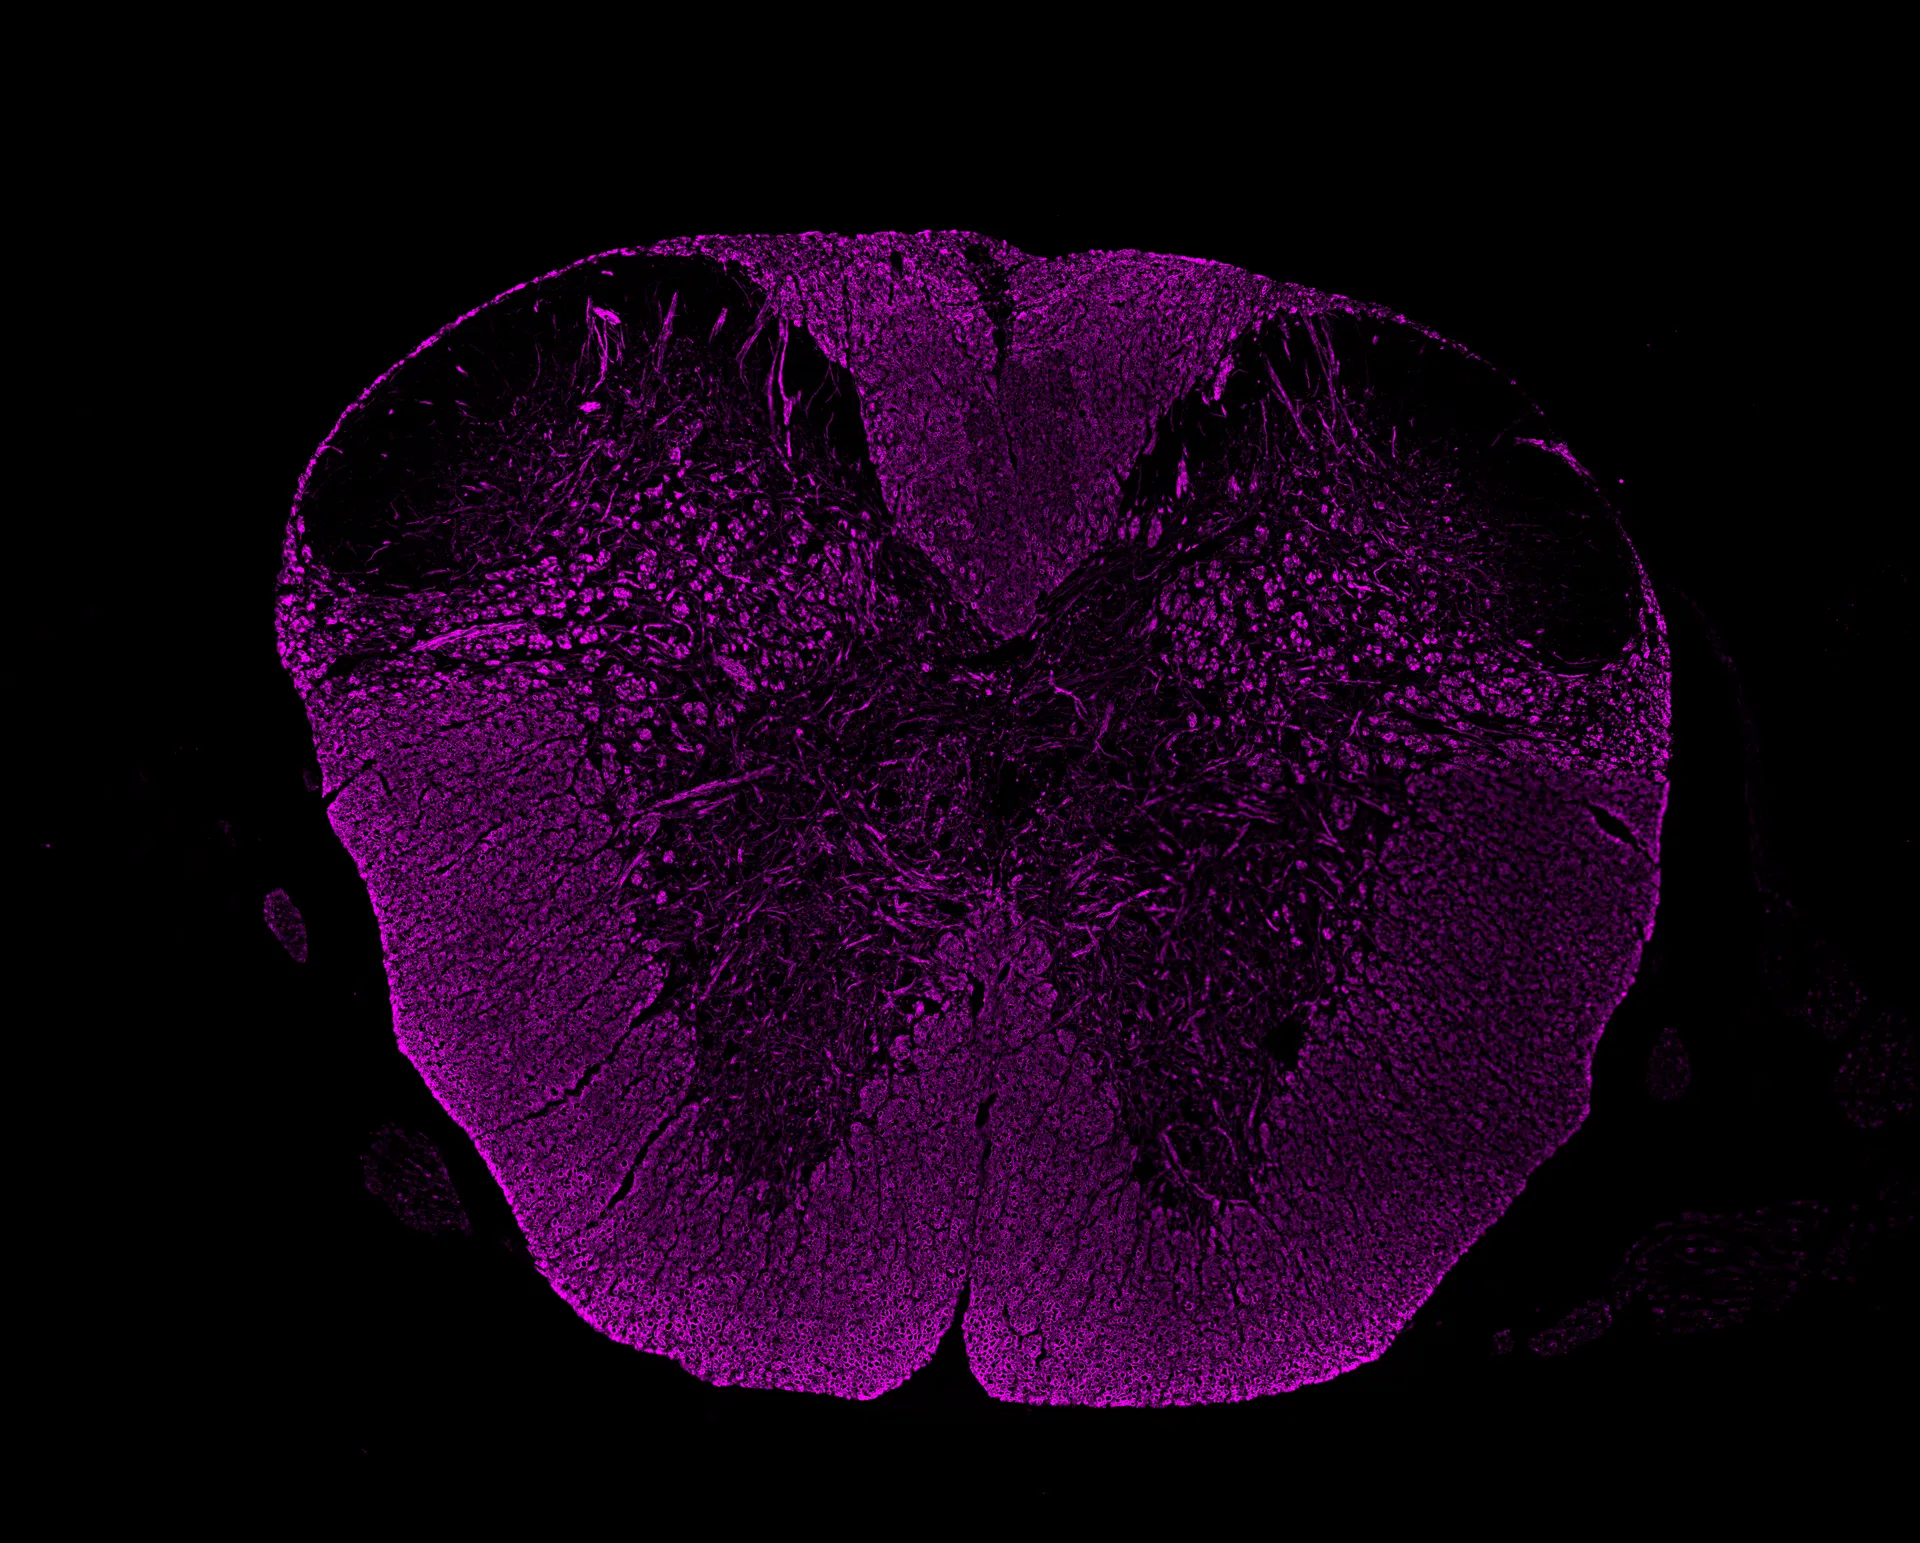

– Assessment of infiltration and demyelination

– Quantification of retinal ganglion cells

Experimentica offers a wide range of single and multiplex immunofluorescence labeling to explore disease pathogenesis and therapeutic targets.